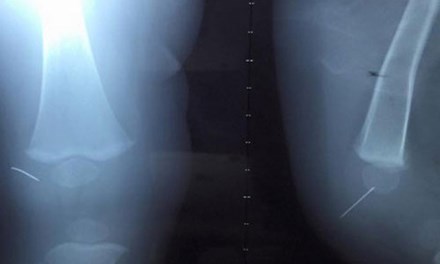

Hình ảnh dị vật trong khớp chân của bé. Ảnh: Tiền Phong |

Các bác sĩ đã phải tăng máy X-quang,hỗ trợ dị vật. Sau hơn 1h, ca phẫu thuật đã tiến hành thành công. Hiện sức khỏe bệnh nhi đang ổn định và tiến tục được theo dõi tại bệnh viện.